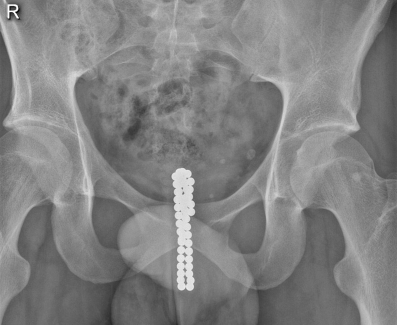

In het Slingeland Ziekenhuis te Doetinchem werd een 21-jarige gezonde jongeman gezien op de Spoedeisende Hulp rond 6:00 uur in de ochtend, met hevige urgency. Hij vertelde de avond ervoor magneetkralen te hebben ingebracht in zijn urethra voor seksuele stimulatie. Ondanks pogingen van de patiënt zelf, lukte het hem maar deels om de magneetkralen te verwijderen. Bij röntgenonderzoek werden metaalhoudende corpora aliena gezien ter hoogte van de urethra prostatica (fig. 3). Een poging tot poliklinische evacuatie van de kralen met een flexibele cystoscoop, was niet succesvol. Dezelfde dag werd de patiënt op de operatiekamer behandeld, waarbij met een resectoscoop, onder zicht, de magneetkralen werden gezien in de urethra prostatica. Er werd voor gekozen om de magneetkralen door te duwen tot in de blaas, omdat er in de urethra onvoldoende grip op de magneetkralen kon worden gekregen. Vanuit de blaas lukte het wel om de magneetkralen te verwijderen, zij het met enige moeite. Het was lastig om de kralen een voor een op te pakken, omdat deze aan de cystoscoop bleven ‘hangen’, door hun magnetische werking. Er werd gebruikgemaakt van een paktang (Olympus) met twee ronde bekdelen (fig. 4). Uiteindelijk zijn alle 49 kralen, met een diameter van 5,5 mm elk, transurethraal verwijderd, waarbij geen blijvende schade is opgetreden.

Figuur 3

Röntgenfoto van het bekken waarop, ter hoogte van de urethra prostatica, een reeks metaalhoudende corpora aliena te zien is.

Levine et al. raden aan om bij een patiënt die zich met LUTS presenteert op SEH ook een corpus alienum in de differentiaaldiagnose op te nemen, ondanks het feit dat een corpus alienum een zeldzaamheid is [1]. Van Ophoven en deKernion beschreven, op basis van een uitgebreide review, dat de verwijdering van corpora aliena in de urethra en blaas afhangt van de grootte en beweeglijkheid van deze corpora aliena [2]. De peniele urethra heeft een doorsnede van 5–6 mm. Daarnaast zijn er drie fysiologische vernauwingen van de mannelijke urethra, namelijk de urethra prostatica, de urethra membranacea en de meatus externus. Zijn de magneetkralen bij inbrengen eenmaal de meatus externa en urethra membranacea gepasseerd, dan is op basis van de locatie, spontane lozing zeer onwaarschijnlijk, zoals zichtbaar is in fig. 3.